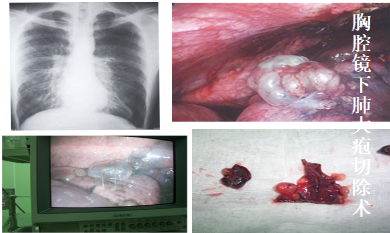

对于肺部良、恶性肿瘤(肺结节或肺大疱等)能行胸腔镜下肺叶乃至肺段切除术,具有创伤小、恢复快、治疗彻底的特点。对胸部食管、食管胃结合处的良恶性肿瘤诊疗经验丰富,治疗规范。对纵膈各类肿瘤亦能做到微创切除,副损伤小等